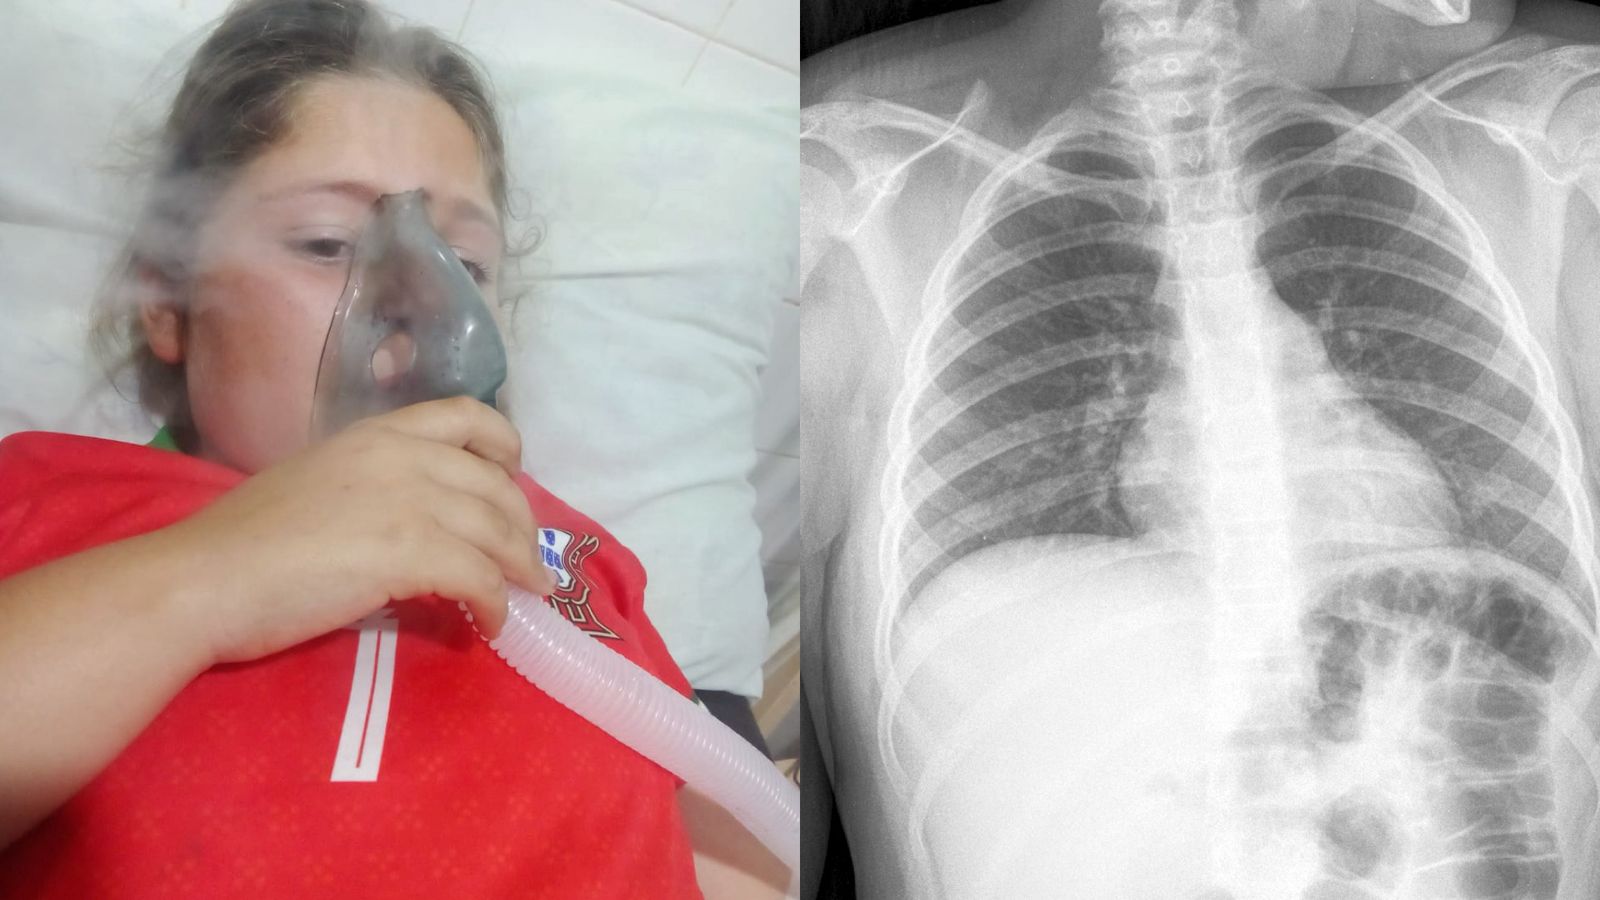

La familia de Manuela Valenzuela, residente de General Delgado, atraviesa una situación desesperante y apela a la solidaridad ciudadana para poder costear los estudios médicos de alta complejidad que necesita su hija de 8 años.

La pequeña padece epilepsia y serios problemas pulmonares, afecciones que ha enfrentado desde hace tiempo, pero cuyo cuadro se ha agravado recientemente, requiriendo atención médica urgente. Los estudios que necesita solo pueden realizarse en Asunción, lo que representa un alto costo económico para la familia.